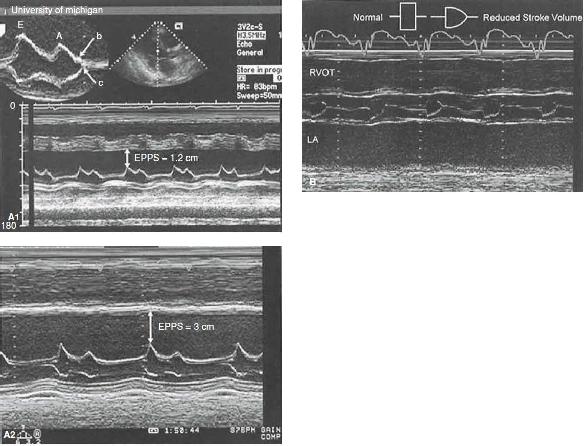

FIGURE 25.10 Left ventricular function. A: M-mode echocardiograms recorded in two patients with significant systolic dysfunction. Top: An E-point septal separation (EPSS) of 1.2 cm (normal M6 mm). Bottom: Recording in a patient with more significant left ventricular systolic dysfunction in which the EPSS is 3.0 cm. Also, note the interrupted closure of the mitral valve with a B bump (top), indicating an increase in the left ventricular end-diastolic pressure. B: M-mode echocardiogram recorded through the aortic valve in a patient with reduced cardiac function and decreased forward stroke volume. Note the rounded closure of the aortic valve, indicating decreasing forward flow at the end of systole. Normal and abnormal aortic valve opening patterns are noted in a schematic superimposed on the figure.

FIGURE 25.10 C: Diagram of cardiac structures from standard tomographic planes: parasternal long-axis view (left), parasternal short-axis view (upper right), and apical four-chamber view (lower right). D: From the esophagus, the probe can be flexed to yield a basal short-axis projection. LA, left atrium; RA, right atrium; RV, right ventricle; RVOT, right ventricular outflow tract.